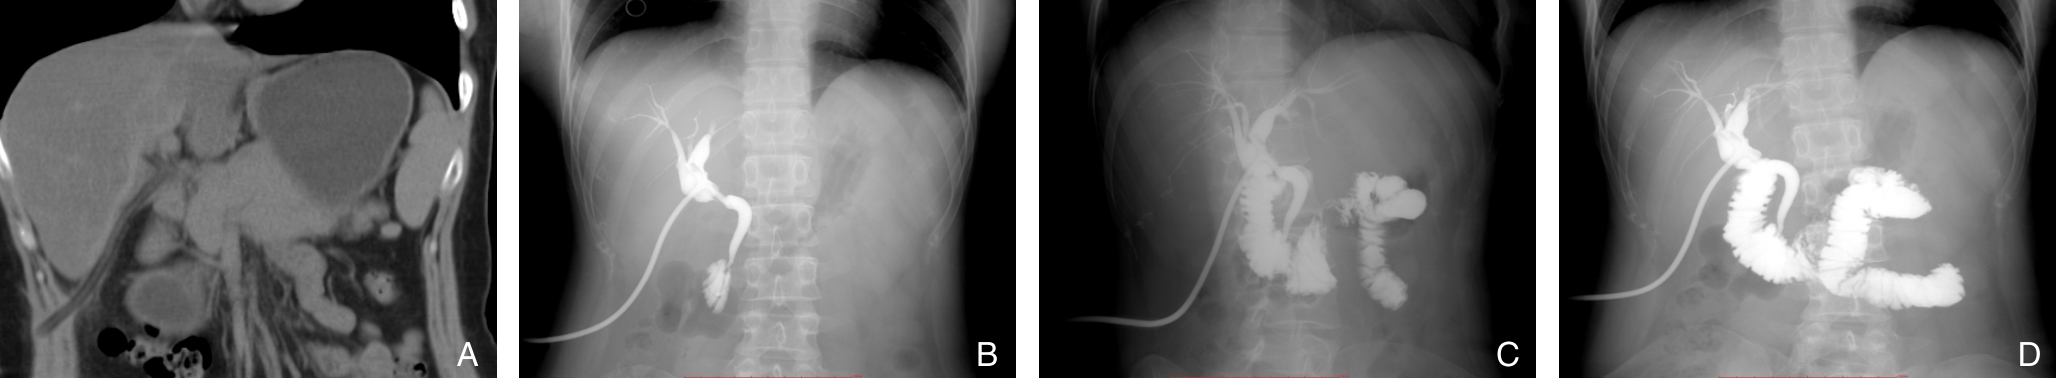

背景与目的 在微创与加速康复理念推动下,减孔腹腔镜技术逐渐应用于胆总管结石治疗,但单孔腹腔镜-胆道镜胆总管探查术的临床价值及其学习过程仍缺乏系统评估。本研究基于倾向评分匹配,比较单孔与三孔腹腔镜-胆道镜胆总管探查术的临床疗效,并分析单孔术式的学习曲线特征。方法 回顾性纳入2022年3月—2025年8月中国人民解放军联勤保障部队第九〇一医院行腹腔镜-胆道镜胆总管探查术的患者,按手术方式分为单孔组与三孔组。采用1∶2倾向评分匹配平衡基线差异。比较两组围手术期指标,包括手术时间、术中出血、术后恢复情况、并发症及住院费用等。以手术时间为评价指标,采用累积求和分析法(CUSUM)分析单孔术式学习曲线。结果 匹配后两组基线资料基本均衡。与三孔组相比,单孔组术后排气时间更短、术后24 h疼痛评分更低、腹腔引流管留置时间更短(均P<0.05),但手术时间更长、住院费用更高(均P<0.05)。两组在术中出血量、术后胆汁漏、术后感染及住院时间等方面差异无统计学意义(均P>0.05)。CUSUM分析显示,单孔腹腔镜-胆道镜胆总管探查术在完成约20例后达到学习曲线拐点,术者操作逐渐稳定。结论 单孔腹腔镜-胆道镜胆总管探查术在保证安全性的前提下,可减轻术后早期疼痛并促进胃肠功能恢复,但以手术时间延长及费用增加为代价。该术式存在一定学习曲线,建议在规范培训及病例选择基础上逐步开展,并优化手术方案。